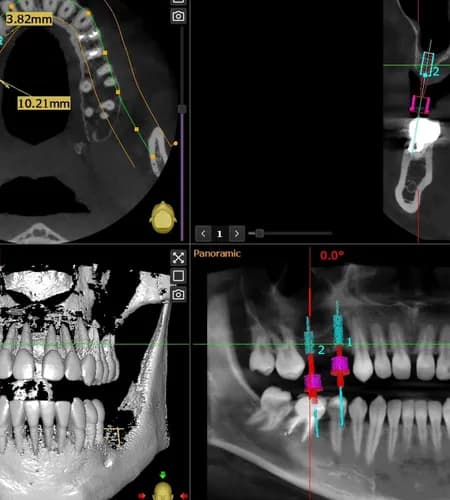

Jeśli odczuwasz dolegliwości, których nie da się jednoznacznie zdiagnozować podczas standardowej wizyty, tomografia komputerowa zębów w Warszawie pozwala dokładnie ocenić stan całej jamy ustnej. Badanie 3D umożliwia szczegółowe zobrazowanie zębów, korzeni, kości oraz tkanek otaczających, dzięki czemu stomatolog w Warszawie może wykryć ukryte stany zapalne, zmiany okołowierzchołkowe czy problemy wymagające leczenia kanałowego lub chirurgicznego. Tomografia jest szybka, bezbolesna i stanowi zaawansowane narzędzie diagnostyczne, szczególnie przy skomplikowanych przypadkach. Na podstawie wyników możliwe jest precyzyjne zaplanowanie leczenia zębów i uniknięcie niepotrzebnych zabiegów. W ramach stomatologii Warszawa możesz skorzystać z nowoczesnej diagnostyki i uzyskać pewną diagnozę. Przez FindOUT możesz bezpośrednio skontaktować się ze stomatologiem, omówić badanie i koszty bez pośredników oraz uzyskać pomoc w swoim języku, co zapewnia komfort i bezpieczeństwo leczenia.